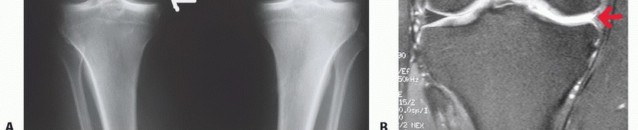

FIG 2

AP weight-bearing bilateral knee views showing subtle medial compartment joint space narrowing of the right knee (

arrow

).

B.

MRI showing deficient medial meniscus.

Anteroposterior (AP) view of both knees in full extension (

FIG 2A

): Look for subtle joint space narrowing.

Magnetic resonance imaging (MRI): to assess menisci, articular cartilage, and subchondral bone (

FIG 2B

)